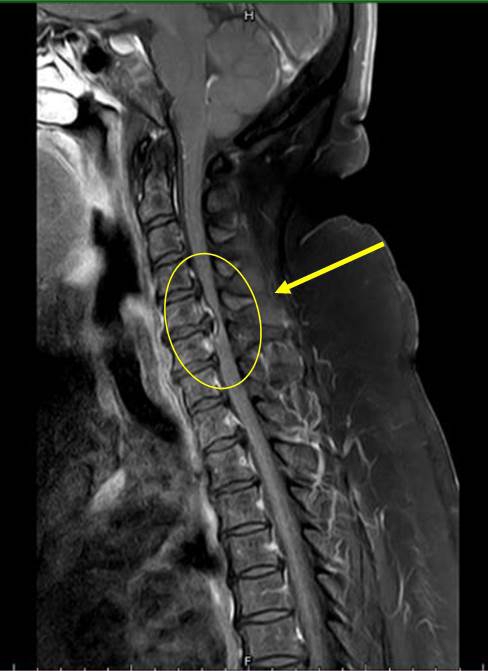

【記者林獻元台中報導】台中豐原一名吳姓四十七歲女性,因長期腰酸背痛不適,近三個月開始下肢無力、麻痛,無法工作,甚至須使用四腳拐杖協助才能走動,在先生陪同至衛生福利部豐原醫院神經外科門診求治,經醫師做神經學評估及安排頸部核磁共振檢查,發現頸部退化椎間盤突出導致壓迫神經使肢體麻痛無力,診療期間病患告知醫師,此次頸椎出問題應該與自己長期胸部豐滿而導致,因為從年輕時胸部就很豐滿也造成自己生活上許多不方便,經神經外科張正一醫師安排頸椎融合手術來改善神經壓迫狀況。

而胸部豐滿女性就像背了兩顆鉛球在胸前,這重擔違反了人體工學,容易造成駝背加劇、胸椎更加後凸,更可能造成「駝背」。神經外科張正一醫師也表示身體為了平衡駝背,易導致頭部自動往前移,讓肩頸痠痛產生,外觀上易變成「永久低頭族」,如此易傷頸椎。